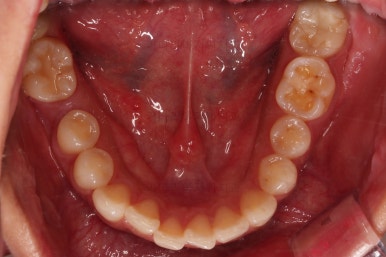

1. 초진

연산동교정치과 초진 시 입안의 모습입니다.

아랫니 어금니가 하나 없어서 주위 치아들이 해당 위치로 쓰러진 상태였습니다.

아랫니는 어금니와 사랑니를 앞으로 당겨옵니다.

물론 다른 치아에 변화를 주지 않기 위해서 미니스크류를 이용합니다.

교합도 잘 맞고 이 뽑은 자리도 틈이 없으며 사랑니 당겨온 자리도 틈새 없이 잘 마무리가 되었네요.